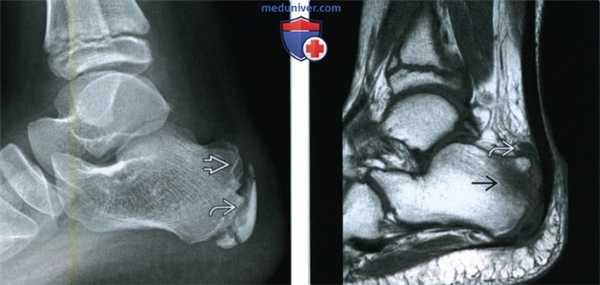

3. МРТ при болезни Севера:

• Отек костного мозга в апофизе заднего отростка пяточной кости и в ее прилежащих отделах

• Передний ахиллобурсит (ретрокальканеальный)

• Паратендинит ахиллова сухожилия:

о Жидкость в паратендинии ахиллова сухожилия

(Левый) Мальчик 12 лет. Выявлена клиническая симптоматика болезни Севера. При рентгенографии голеностопного сустава в боковой проекции определяются склерозированный и фрагментированный апофиз пяточной кости, а также зубчатый контур метафиза, что часто можно наблюдать и у детей без клинической симптоматики. Симптомы болезни Севера могут выявляться при тендинопатии ахиллова сухожилия, реакции апофиза на избыточную тягу ахиллова сухожилия или стресс-переломе пяточной кости.

(Правый) Пациент, у которого выявлена клиническая симптоматика болезни Севера. При МРТ в сагиттальной плоскости на Т1ВИ визуализируются отек костного мозга пяточной кости и признаки переднего ахиллобурсита.